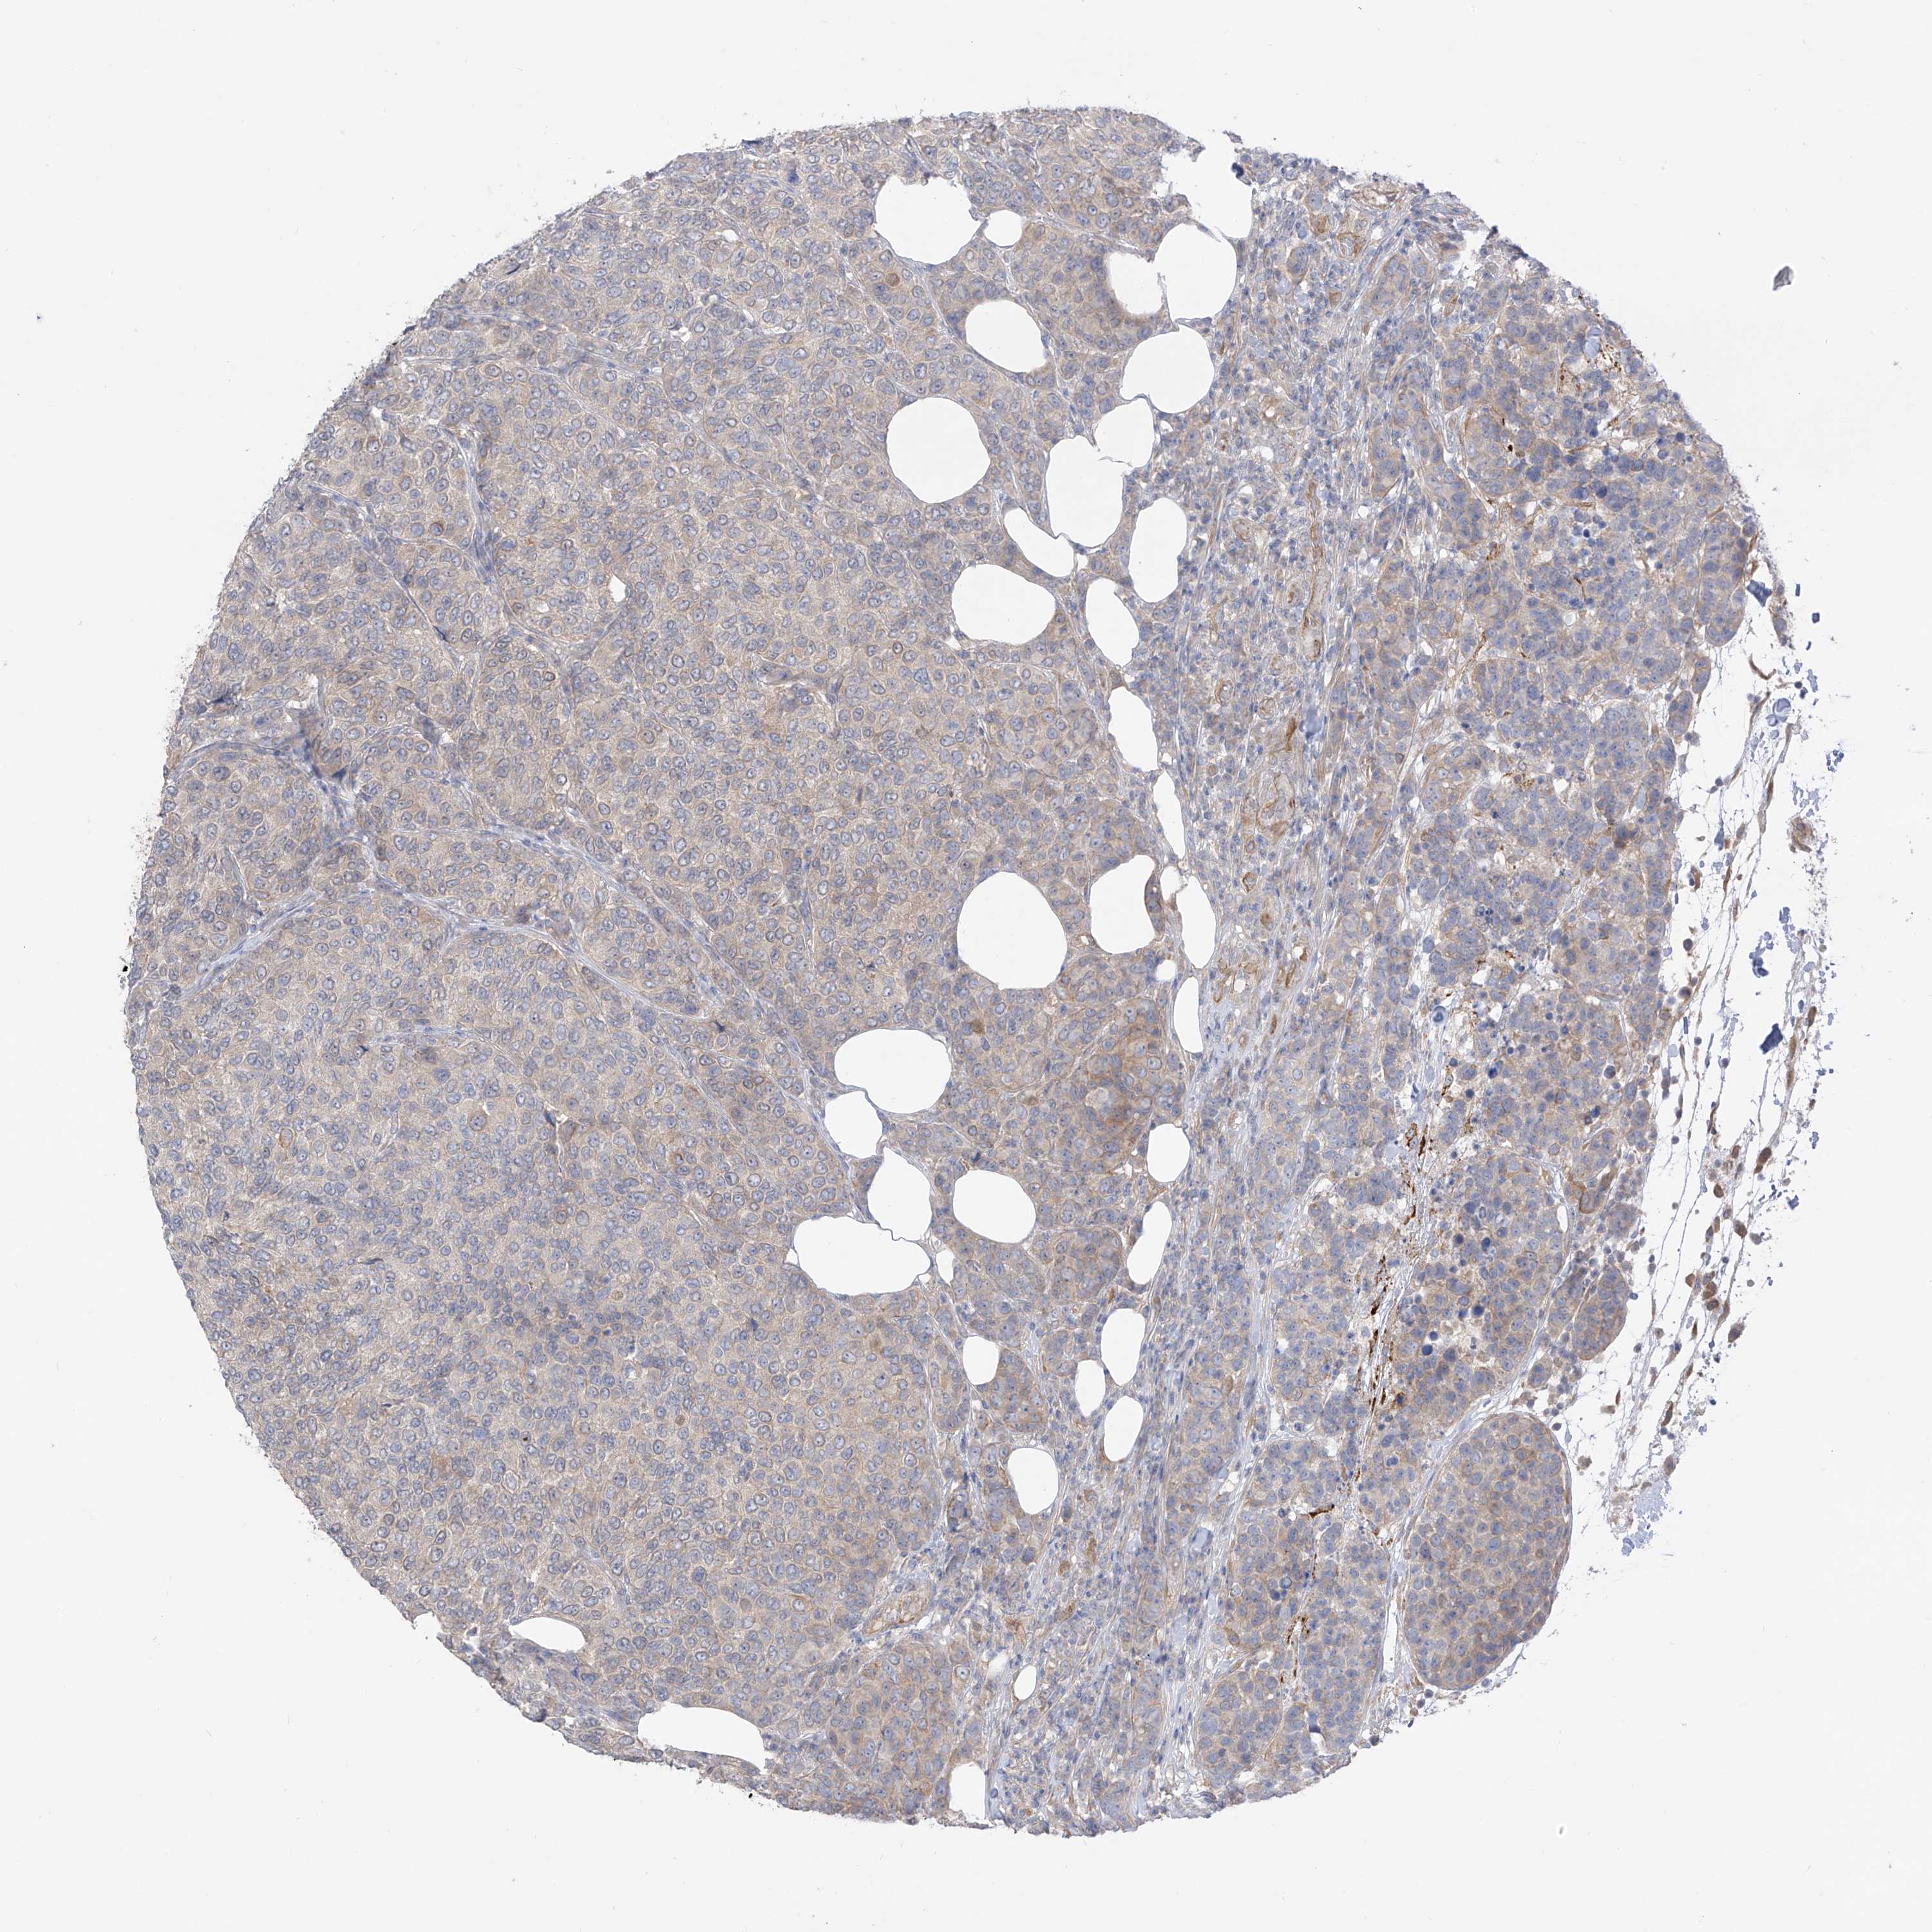

CANCER BREAST CANCER Show tissue menu

BRCA TCGA BRCA VALIDATION PROTEIN EXPRESSION